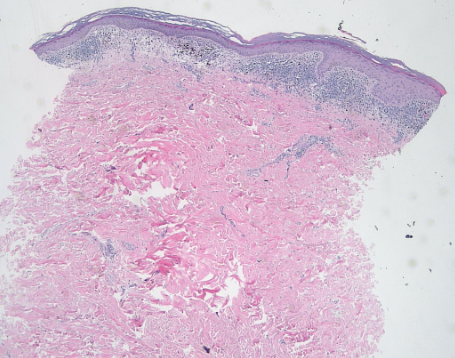

DERMATOHISTOPATHOLOGY:

The histopathological examination revealed several notable features consistent with a lichenoid tissue reaction. There was a band-like lichenoid infiltrate present in the papillary dermis, along with interface vacuolar degeneration affecting the basal cell layer of the epidermis. Additionally, pigmentary incontinence was observed in the upper dermis, indicative of melanin leakage. Hypergranulosis was noted, characterized by an increase in granules within the keratinocytes. The rete ridges exhibited a saw-tooth appearance, and Civatte bodies, which are apoptotic keratinocytes, were also identified.